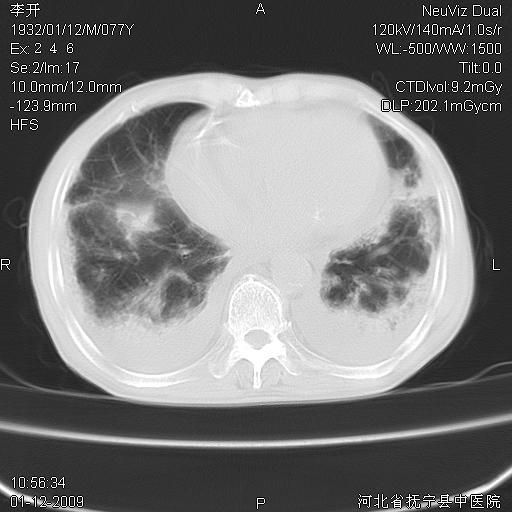

以下是引用黑白光影在2009-1-19 16:49:00的发言:[br]心衰肺水肿;心包、胸腔积液;冠脉钙化;肺部感染。